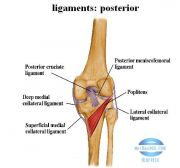

| 2021年7月26日 (一) 20:03 | 膝关节韧带后面观.jpg (文件) |  |

35 KB | Uploaded with SimpleBatchUpload | 3 |